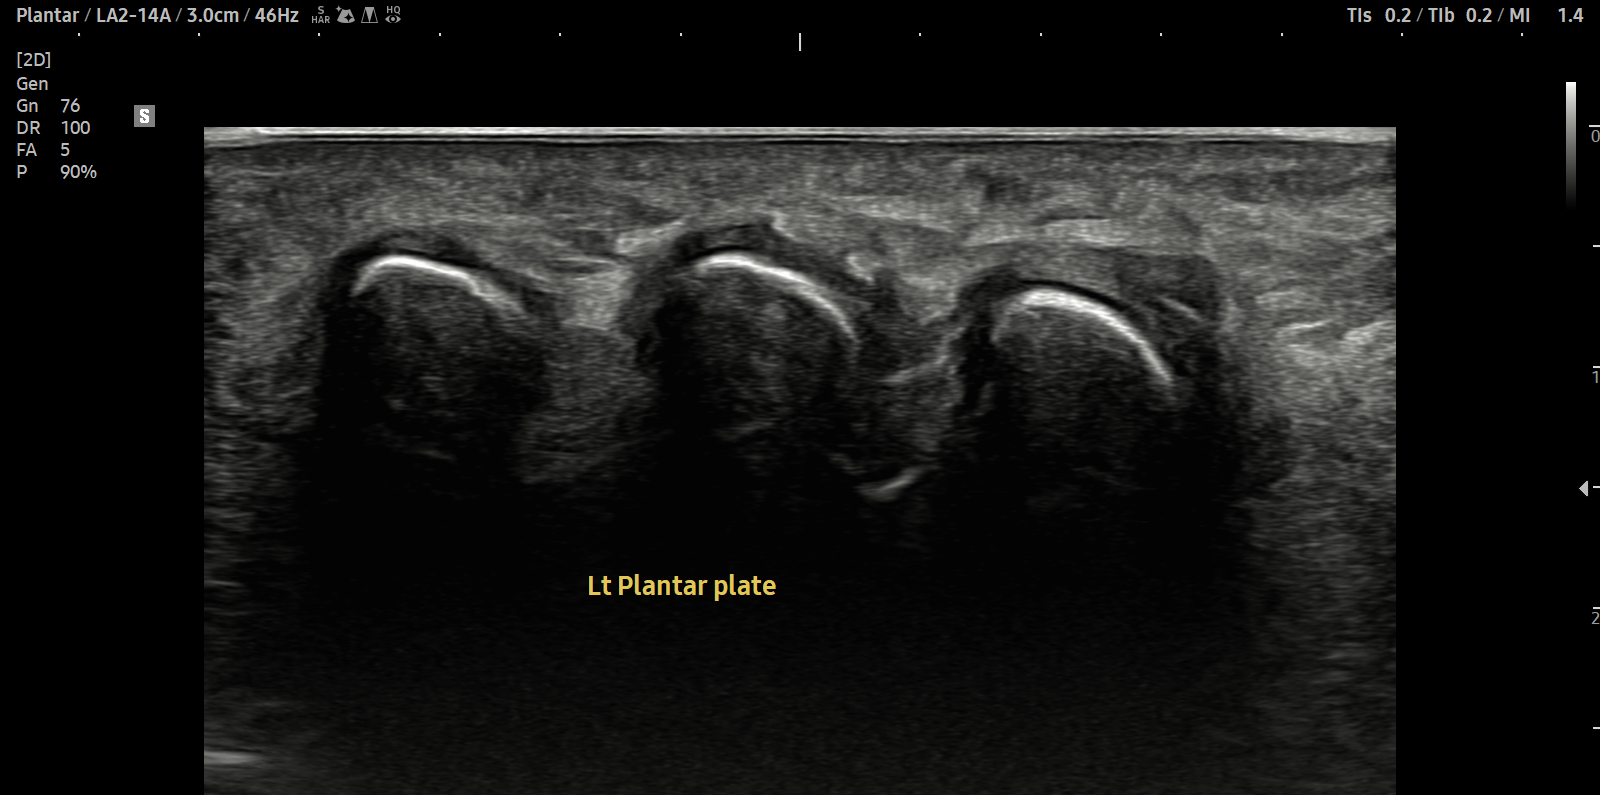

치료 후기에 사용된 전/후 검사 사진은 동일 인물의 결과이며 각 지점 동일 조건에서 촬영되었습니다.

개인에 따라 치료 결과에 차이가 있을 수 있으며, 부작용이 발생할 수 있습니다. 내원 후 충분한 상담을 받으시고 치료를 진행하시면 됩니다.

- 치료기간 : 25 .5 30 . ~ 25 . 6 .27

- 치료횟수 : 5 회(dna 1cycle)